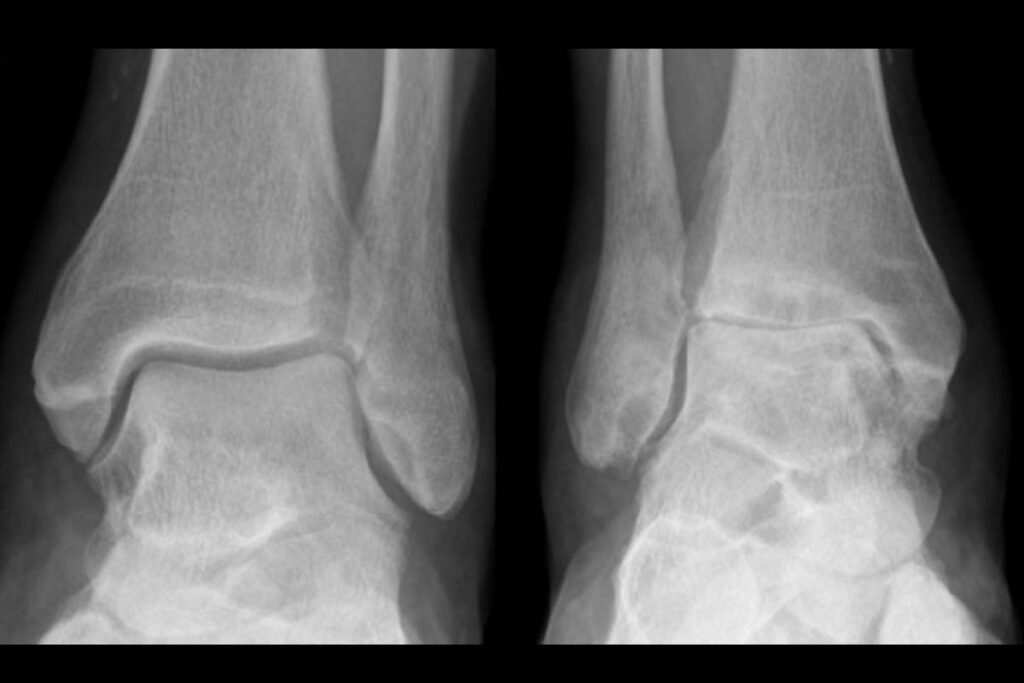

Exemplo de um tornozelo normal e um tornozelo com artrose.

Tipo3A | Acomete o tornozelo | 20% |